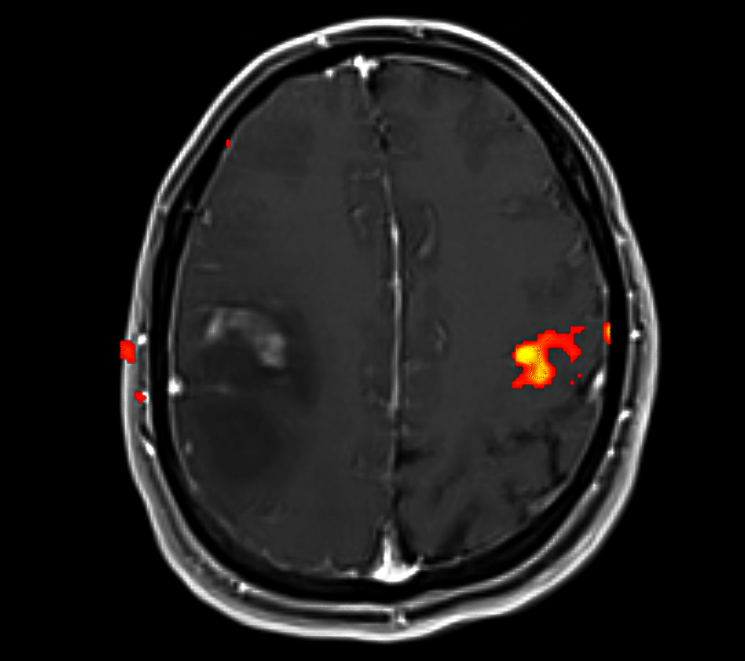

• Functional Mapping for Tumor Resection: For patients with brain tumors, especially those located near or within functional regions, fMRI helps identify the relationship between the tumor and critical brain functions. This allows neurosurgeons to plan the resection in a way that maximizes tumor removal while minimizing damage to essential brain areas. Tumors located near the motor cortex, speech areas, or visual pathways require careful planning to avoid impairing these vital functions.

Functional MRI © ENI